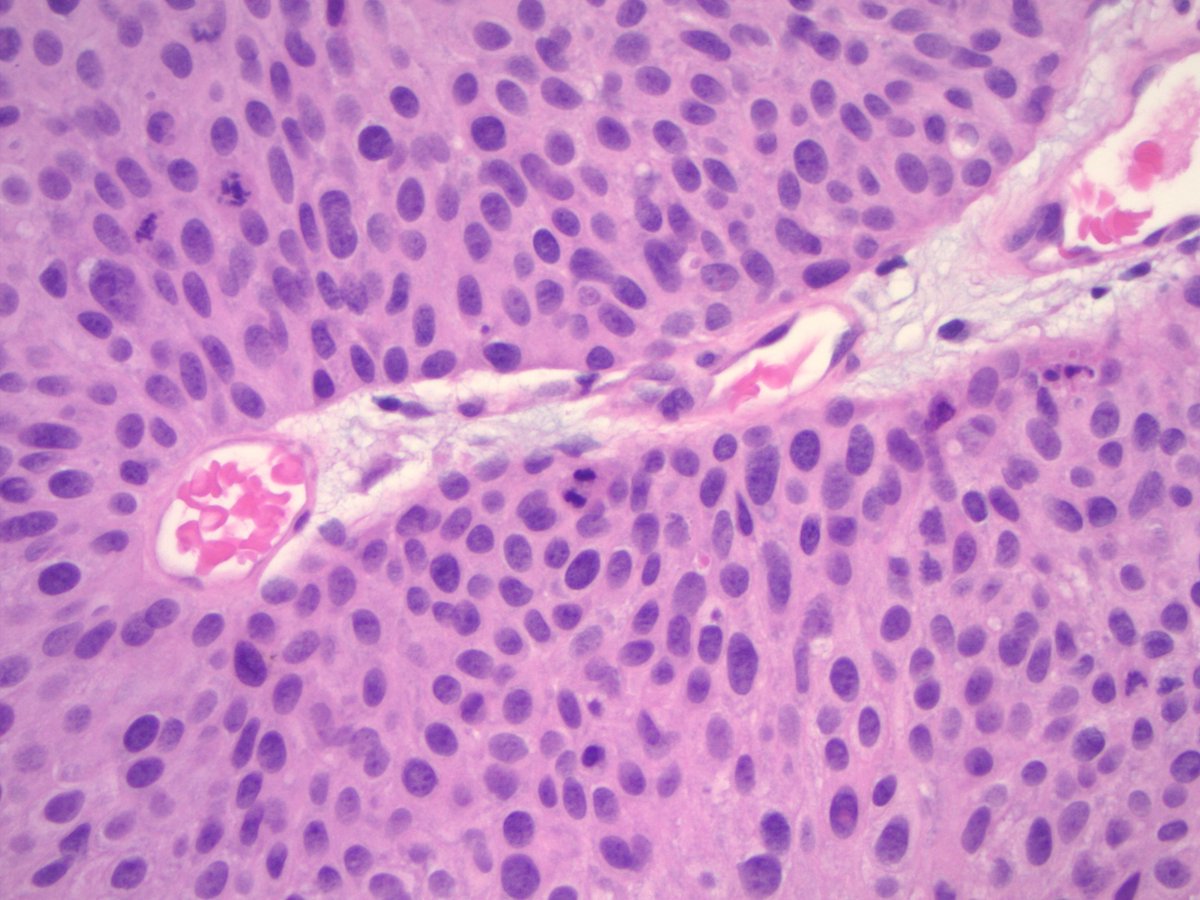

What can you tell me about the patient? Obviously, have to figure out what it is, first. #PediPath #PathTwitter #Path2Path #PathMatch26 X4, X10, X10, X20

leon_metlay's tweet image. What can you tell me about the patient? Obviously, have to figure out what it is, first.

#PediPath #PathTwitter #Path2Path #PathMatch26

X4, X10, X10, X20